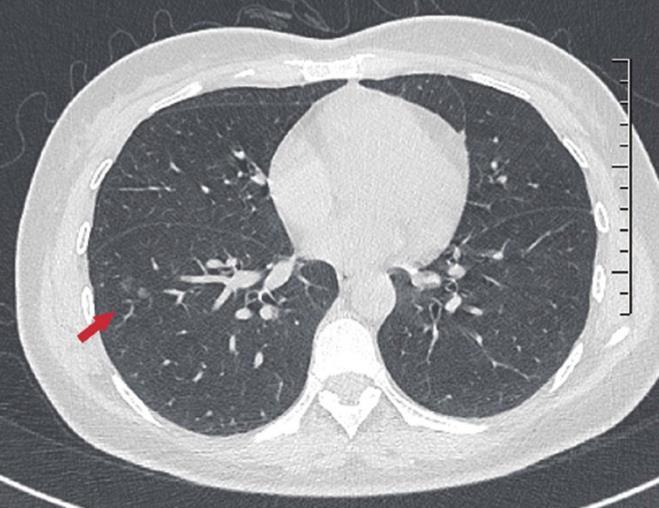

a.两肺见数个小结节

b.数个小结节有一个增大